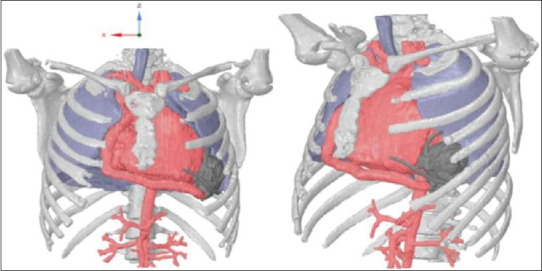

Patient-specific computerized tomography (CT) scan image data were obtained as was the CT image of a Medtronic HeartWare Ventricular Assist Device (HVAD) pump [Figure 2]. The dimension required is mostly 512 × 512 × 523 slices, and voxel spacing is around 0.5 × 0.5 × 0.5. The images contained proper resolution in all three axes. ITK-snap GUI software was used to perform the segmentation operations in all these CT images [Figure 3]. The quality of the segmentation labels mainly depends on the input image data, and image enhancement using thresholding was very useful in identifying the region of interests in the presegmentation mode. After segmentation, presurgical model was created [Figure 4]. Using VR toolbox-oculus touch controllers, the operating surgeon could navigate in and around the heart spatially and also pick and place the LVAD by holding them [Figure 5]. The oculus camera rig helps the surgeons in visualizing the whole environment in a virtual three-dimensional screen or glasses worn on the head with exceptional clarity [Figure 6 and Video 2]. On a traditional two-dimensional navigational screen, the depth perception cannot be expected, wherein it is a default-added, major advantageous feature in the VR environment. While performing the preplanning, this depth perception gives more insight to the surgeons about spatial navigation from where they are inside the thoracic cavity.

Figure 4.

Three preplanning views of - the dilated heart, heart with ribcage and lungs, and left ventricular assist device to be used

Using the VR study, the ideal spot of insertion of the LVAD on the heart could be determined to confirm ideal inflow cannula position and ensure the possibility of chest closure. The dimple of the LAD is quite easily visible making “registration,” an ability to choose a point on the VR and locate it during surgery, in relation to the LAD, possible. We could confirm that the inflow cannula will not impinge on the mitral valve. He was hence offered an LVAD implant.

Our aim was to use advanced technology to assist surgeons-in choosing the device, selecting optimal position for left ventricle wall coring and deciding ideal position to place the intra thoracic ventricular assist device pump-with the goal to optimize pump function, avoid secondary migration after chest closure, and minimize thromboembolic risk due to mechanical and hemodynamic factors in an individual patient.

Major requirements for correct placement of LVAD inflow cannula include coaxiality with the mitral valve orifice, nonconflict with the interventricular septum, and left ventricular cavity walls. Hence, with the help of CT scan through dedicated widgets, mitral valvular orifice was identified. Along with that, organs of interest for LVAD implantation such as heart, lungs, and ribcages also delineated. All these landmarks were considered to determine the possibility of chest closure after LVAD implantation. Both LVAD and graft connecting the outlet of the pump to aorta will be placed in the thoracic cavity and all these factors will also influence the positional change of the adjacent organs. This will ultimately take into consideration the intrathoracic placement with respect to the rigid chest wall, the identification of optimal sites for both apical coring and ascending aortic outflow, including performance of intracavitary fluidic simulations.

This tool is really handy in visualizing the orientation of the inflow cannula with respect to the septum of the heart. Normally, surgeons would not be able to see through cardiac muscles as its wall occludes the view while implanting the LVAD. This torch is added with any of the hand in Oculus controls, and when it is directed toward the heart, it would cull the occluding surfaces while performing the virtual placing of the LVAD using the other hand. Subsequently, the software suggests ideal LVAD implantation site and left ventricular coring location, which maximize mitral valve coaxiality in the individual patient. The software also shows the overlap between the virtually implanted LVAD and the osseous chest wall, to help the surgeon estimate the risk of conflict and device migration from the intended position after chest closure.